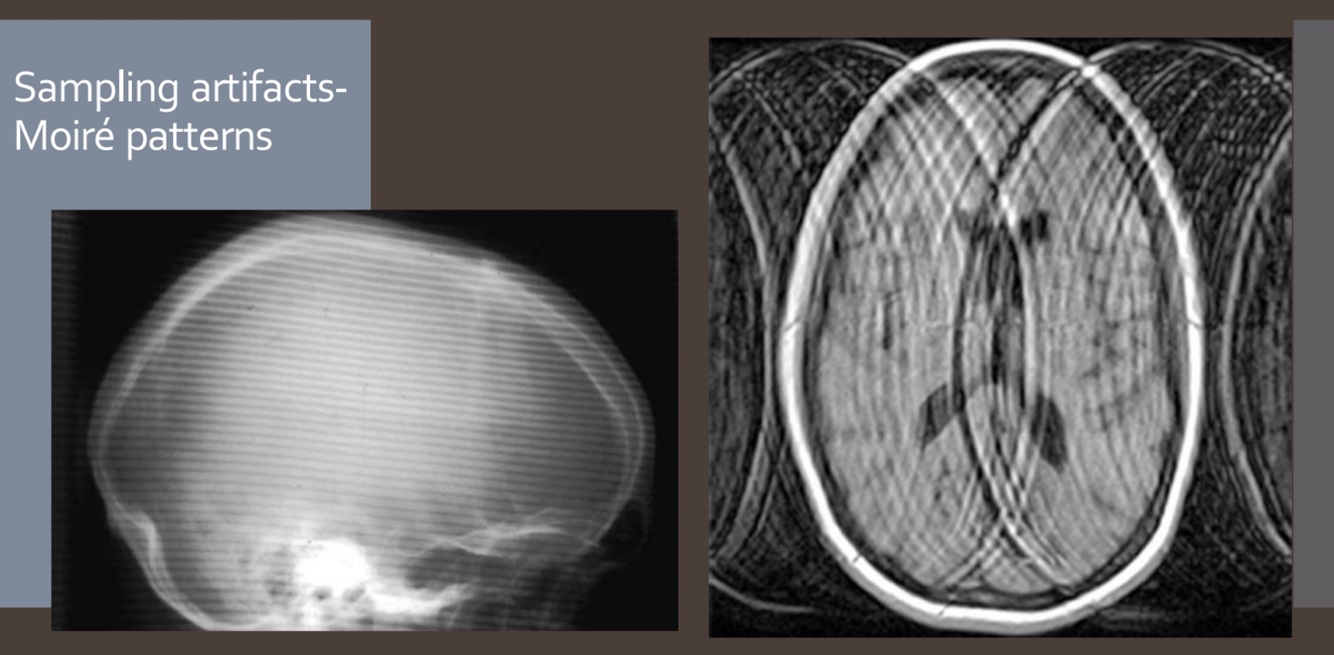

Step 2 sampling: Moire Pattern

A

-Sampling error

-If the sampling rates are too low, specific artifacts occur called moire patterns